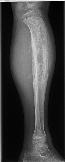

左胫骨骨肉瘤

病史: 入院情况:因“左小腿疼痛伴肿胀14日”入院。查体:左小腿下段肿胀明显,触压有疼痛,余无特殊。

诊断与讨论: 左胫骨骨肉瘤

分类: 骨骼与肌肉系统骨肿瘤与肿瘤样病变骨肉瘤